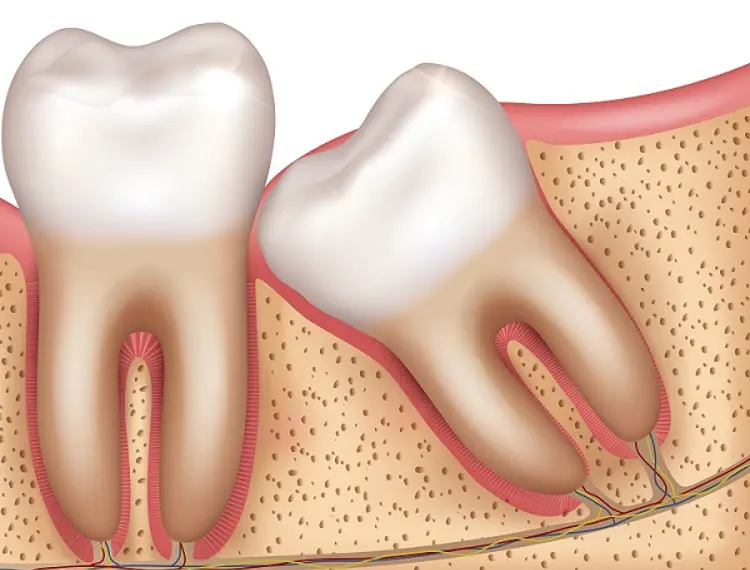

What are impacted wisdom teeth?

Wisdom teeth are often impacted, meaning something is stopping them from pushing all the way into the mouth.

For many people, wisdom teeth are unable to move from under the gums and into the mouth as the rest of the teeth do. Most people do not have enough space in their jaws for wisdom teeth to easily push through the gums. If there is not enough space, the wisdom tooth will become impacted. Impacted teeth sit under the gum or partially through the gum so only a small portion of the tooth can be seen in the mouth.

A wisdom tooth may sit on an angle that is causes it to bump into the tooth in front. This can stop the tooth it from moving into the mouth.